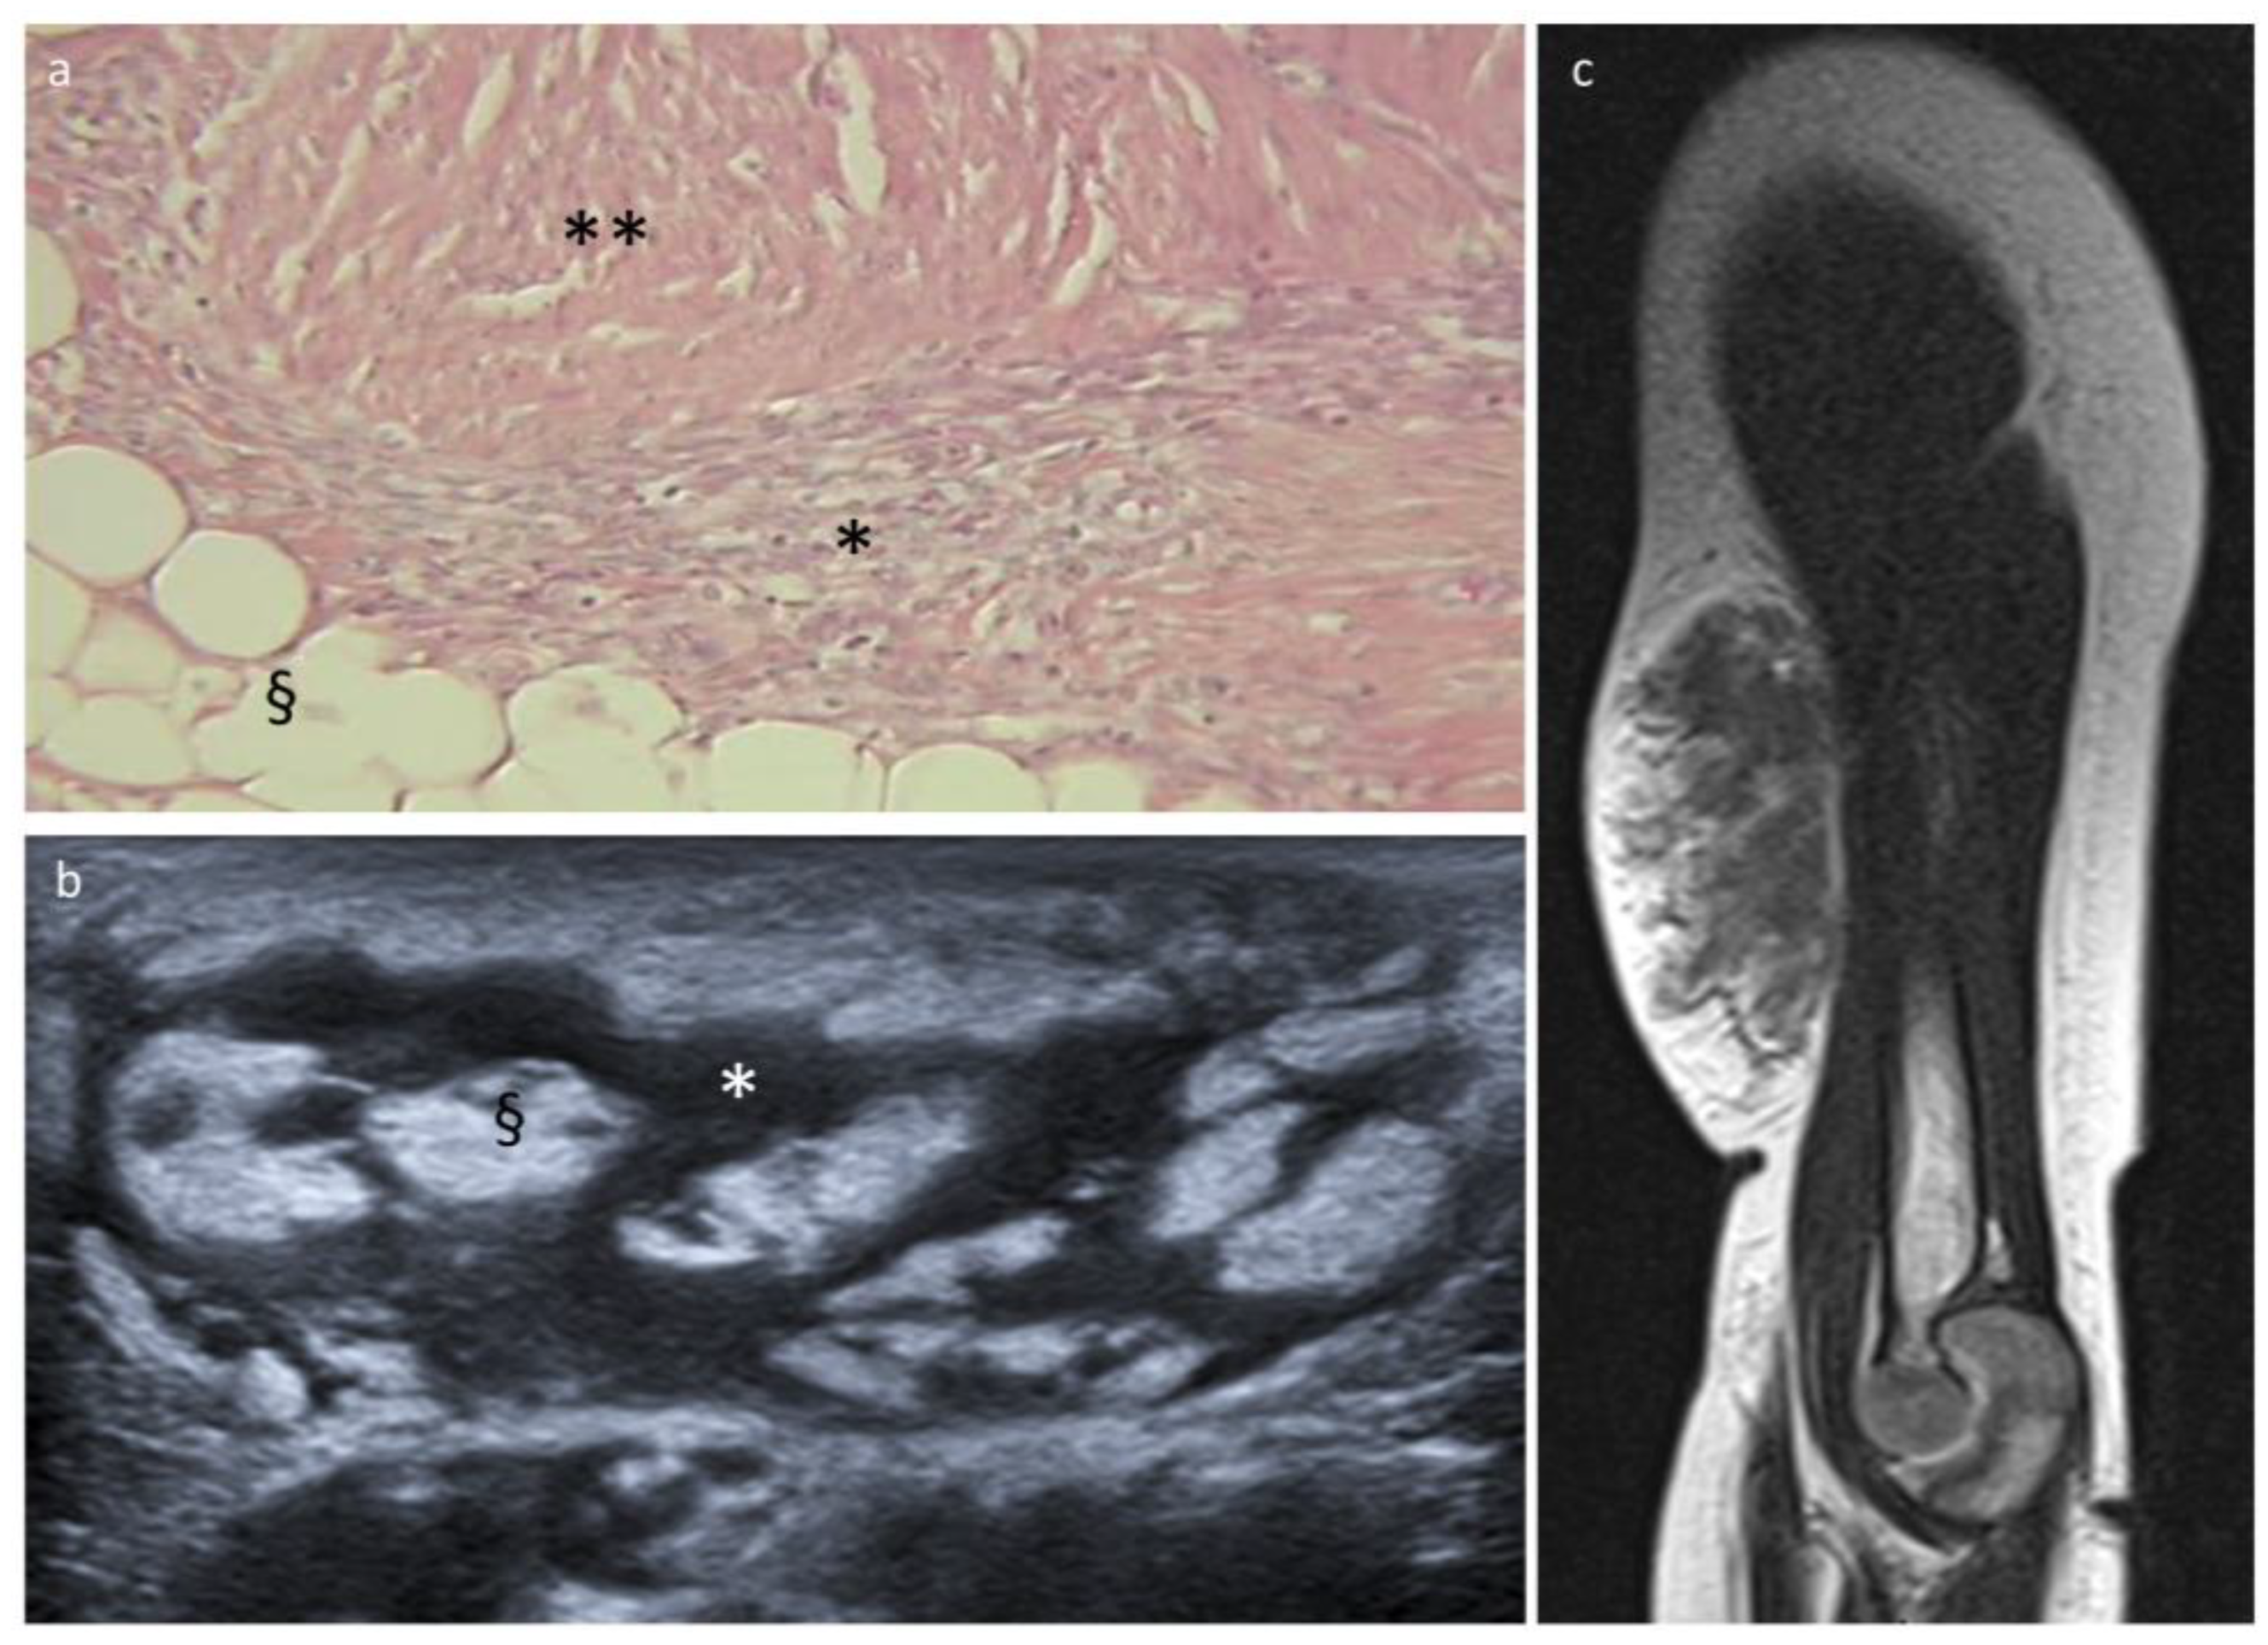

3.2. Fibrous Hamartoma of Infancy

3.3. Lipofibromatosis